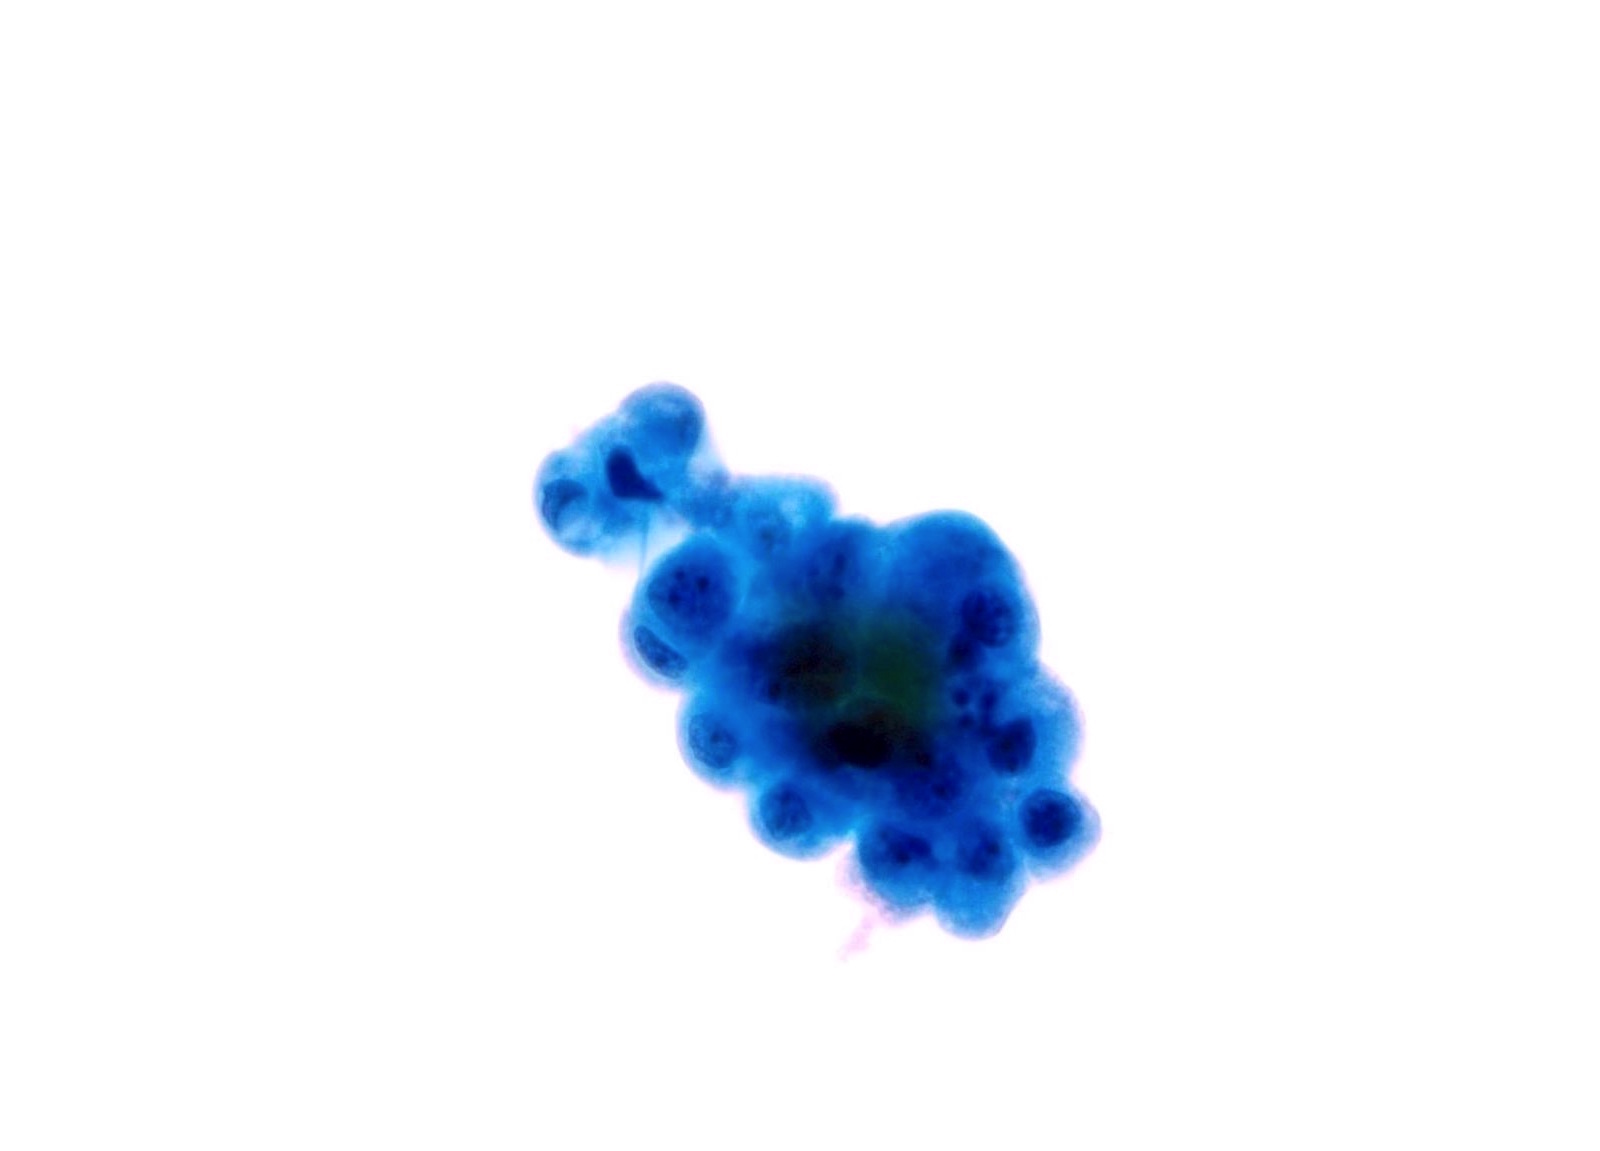

High Grade Urothelial Carcinoma (HGUC)

-

- HGUC is diagnosed on the basis of this criteria according to the Paris System consensus:

- Cellularity; at least 5 - 10 abnormal cells

- N:C ratio: 0.7 or greater

- Nucleus: moderate to severe hyperchromasia

- Nuclear membrane: markedly irregular

- Chromatin: coarse / clumped

- Other notable cytomorphologic features of HGUC are

- Cellular pleomorphism

- Marked variation in cellular size and shapes. i.e., oval, rounded, elongated or plasmacytoid (comet cells)

- Scant, pale or dense cytoplasm

- Prominent nucleoli

- Mitoses

- Necrotic debris

- Inflammation